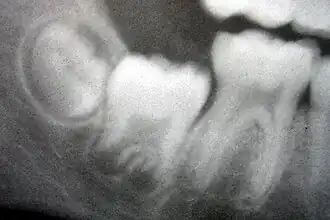

_showing_Deciduous(Milky_or_Primary)_Tooth_75_and_developing_crown_of_Permanent_or_Secondary_Teeth_35%252C_36_and_37.jpg)